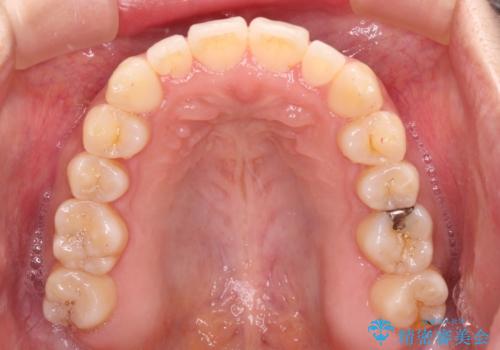

すきっ歯とオープンバイトをインビザラインで改善

- 前歯の上下スペースと前歯の隙間を気にして来院された患者様です。

インビザラインにより上下の前歯の隙間を閉じていくこととしました。

上下の隙間に舌が入り込むことが、すきっ歯やオープンバイトの原因であったため、舌の筋肉のトレーニングも並行して行い、後戻りの抑制を図りました。